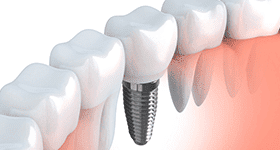

インプラントとは何ですか?歯科用インプラントとは、チタンでできた人工歯根のことです。インプラント治療では、このインプラントを顎の骨に埋め込み、先端に人工歯を装着することで歯を補います。入れ歯よりも自然に近い咬み心地が得られます。

被せ物が出来上がったら装着し、噛み合わせを調整します。緊密に調整することで、より長くインプラントをもたせることができます。

インプラントの治療は、歯が入ったら終わりではありません。インプラントは骨とはくっつきますが歯茎とはくっつかないため、歯茎とインプラントの間に汚れが溜まると「インプラント周囲炎」という症状を引き起こすことがあります。